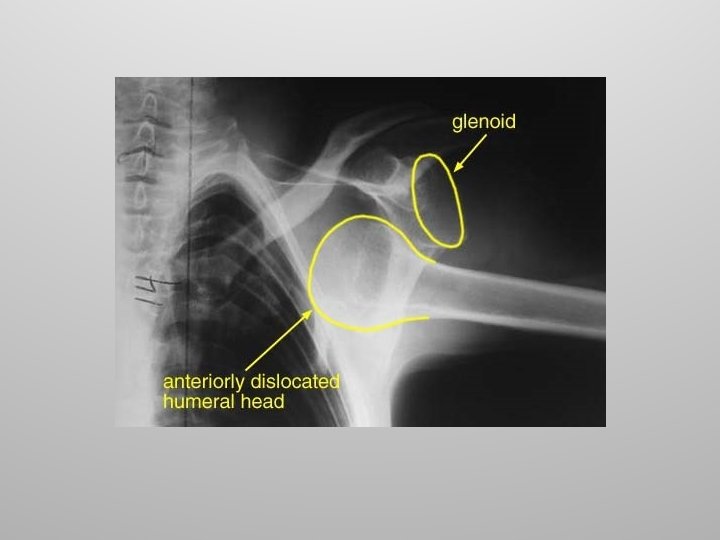

Shoulder (Glenohumeral) Joint The large head of the humerus fits into the glenoid cavity of the scapula. The cavity is extended by a fibrocartilage ring called the glenoid labrum. Connective tissue support comes from three groups of ligaments.

Shoulder Injuries Rotator Cuff Because of its mobility, the stability of the shoulder joint has been sacrificed. Anterior dislocations are the most common along with damage to the rotator cuff muscles due to severe circumduction.